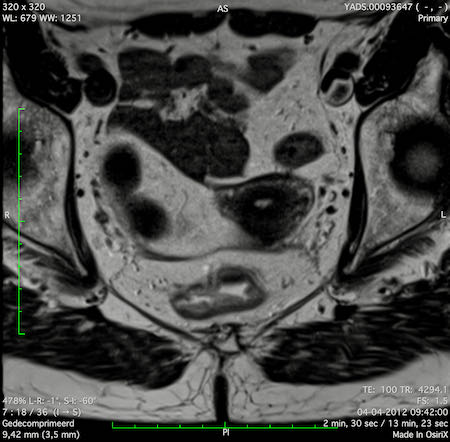

Hình ảnh

Các hình ảnh được cung cấp cho thấy ung thư biểu mô tế bào nhẫn với tình trạng dày lan tỏa thành trực tràng, hình ảnh bia bắn điển hình, và sự xâm lấn mỡ mạc treo trực tràng.